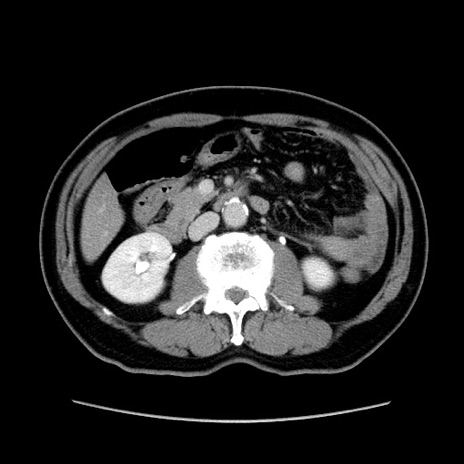

症例34(横断像)

【症例】60歳代 男性

【主訴】右鼠径部膨隆

【現病歴】1年程前より右鼠径部膨隆あり。自己にて還納可能だったため放置していた。3時間前より右鼠径部の脱出を認め、還納困難となり受診。

【身体所見】右鼠径部に小児頭大の膨隆あり。弾性硬であり、用手還納は困難。左鼠径部にも膨隆を認める。脱出はなし。

【データ】WBC 15500、CRP 測定なし